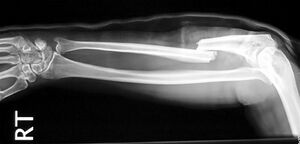

Gebrochener Arm - Speiche - Jane Agnes commons.wikimedia.org, CC BY-SA 3.0

Mit Hilfe einer Röntgenaufnahme wird der Schweregrad der Verletzung abgeklärt. Es erfolgt entweder eine Behandlung mit Gips oder eine operative Versorgung. In der Rehabilitation unterstützen Mobilisations-, Kräftigungs-, Koordinations- und Ausdauerübungen den Heilungsprozess wesentlich. Die volle sportliche Belastbarkeit ist, je nach Bruchart, erst nach vielen Wochen der völligen Bruchheilung gegeben.